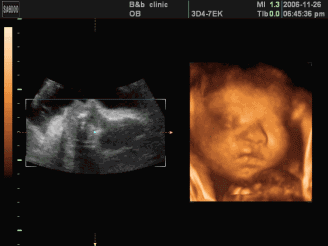

表情丰富的小宝宝,时嘟嘟嘴时而抿嘴唇

以后让你去学表演吧,力压现在当红小鲜肉哦!